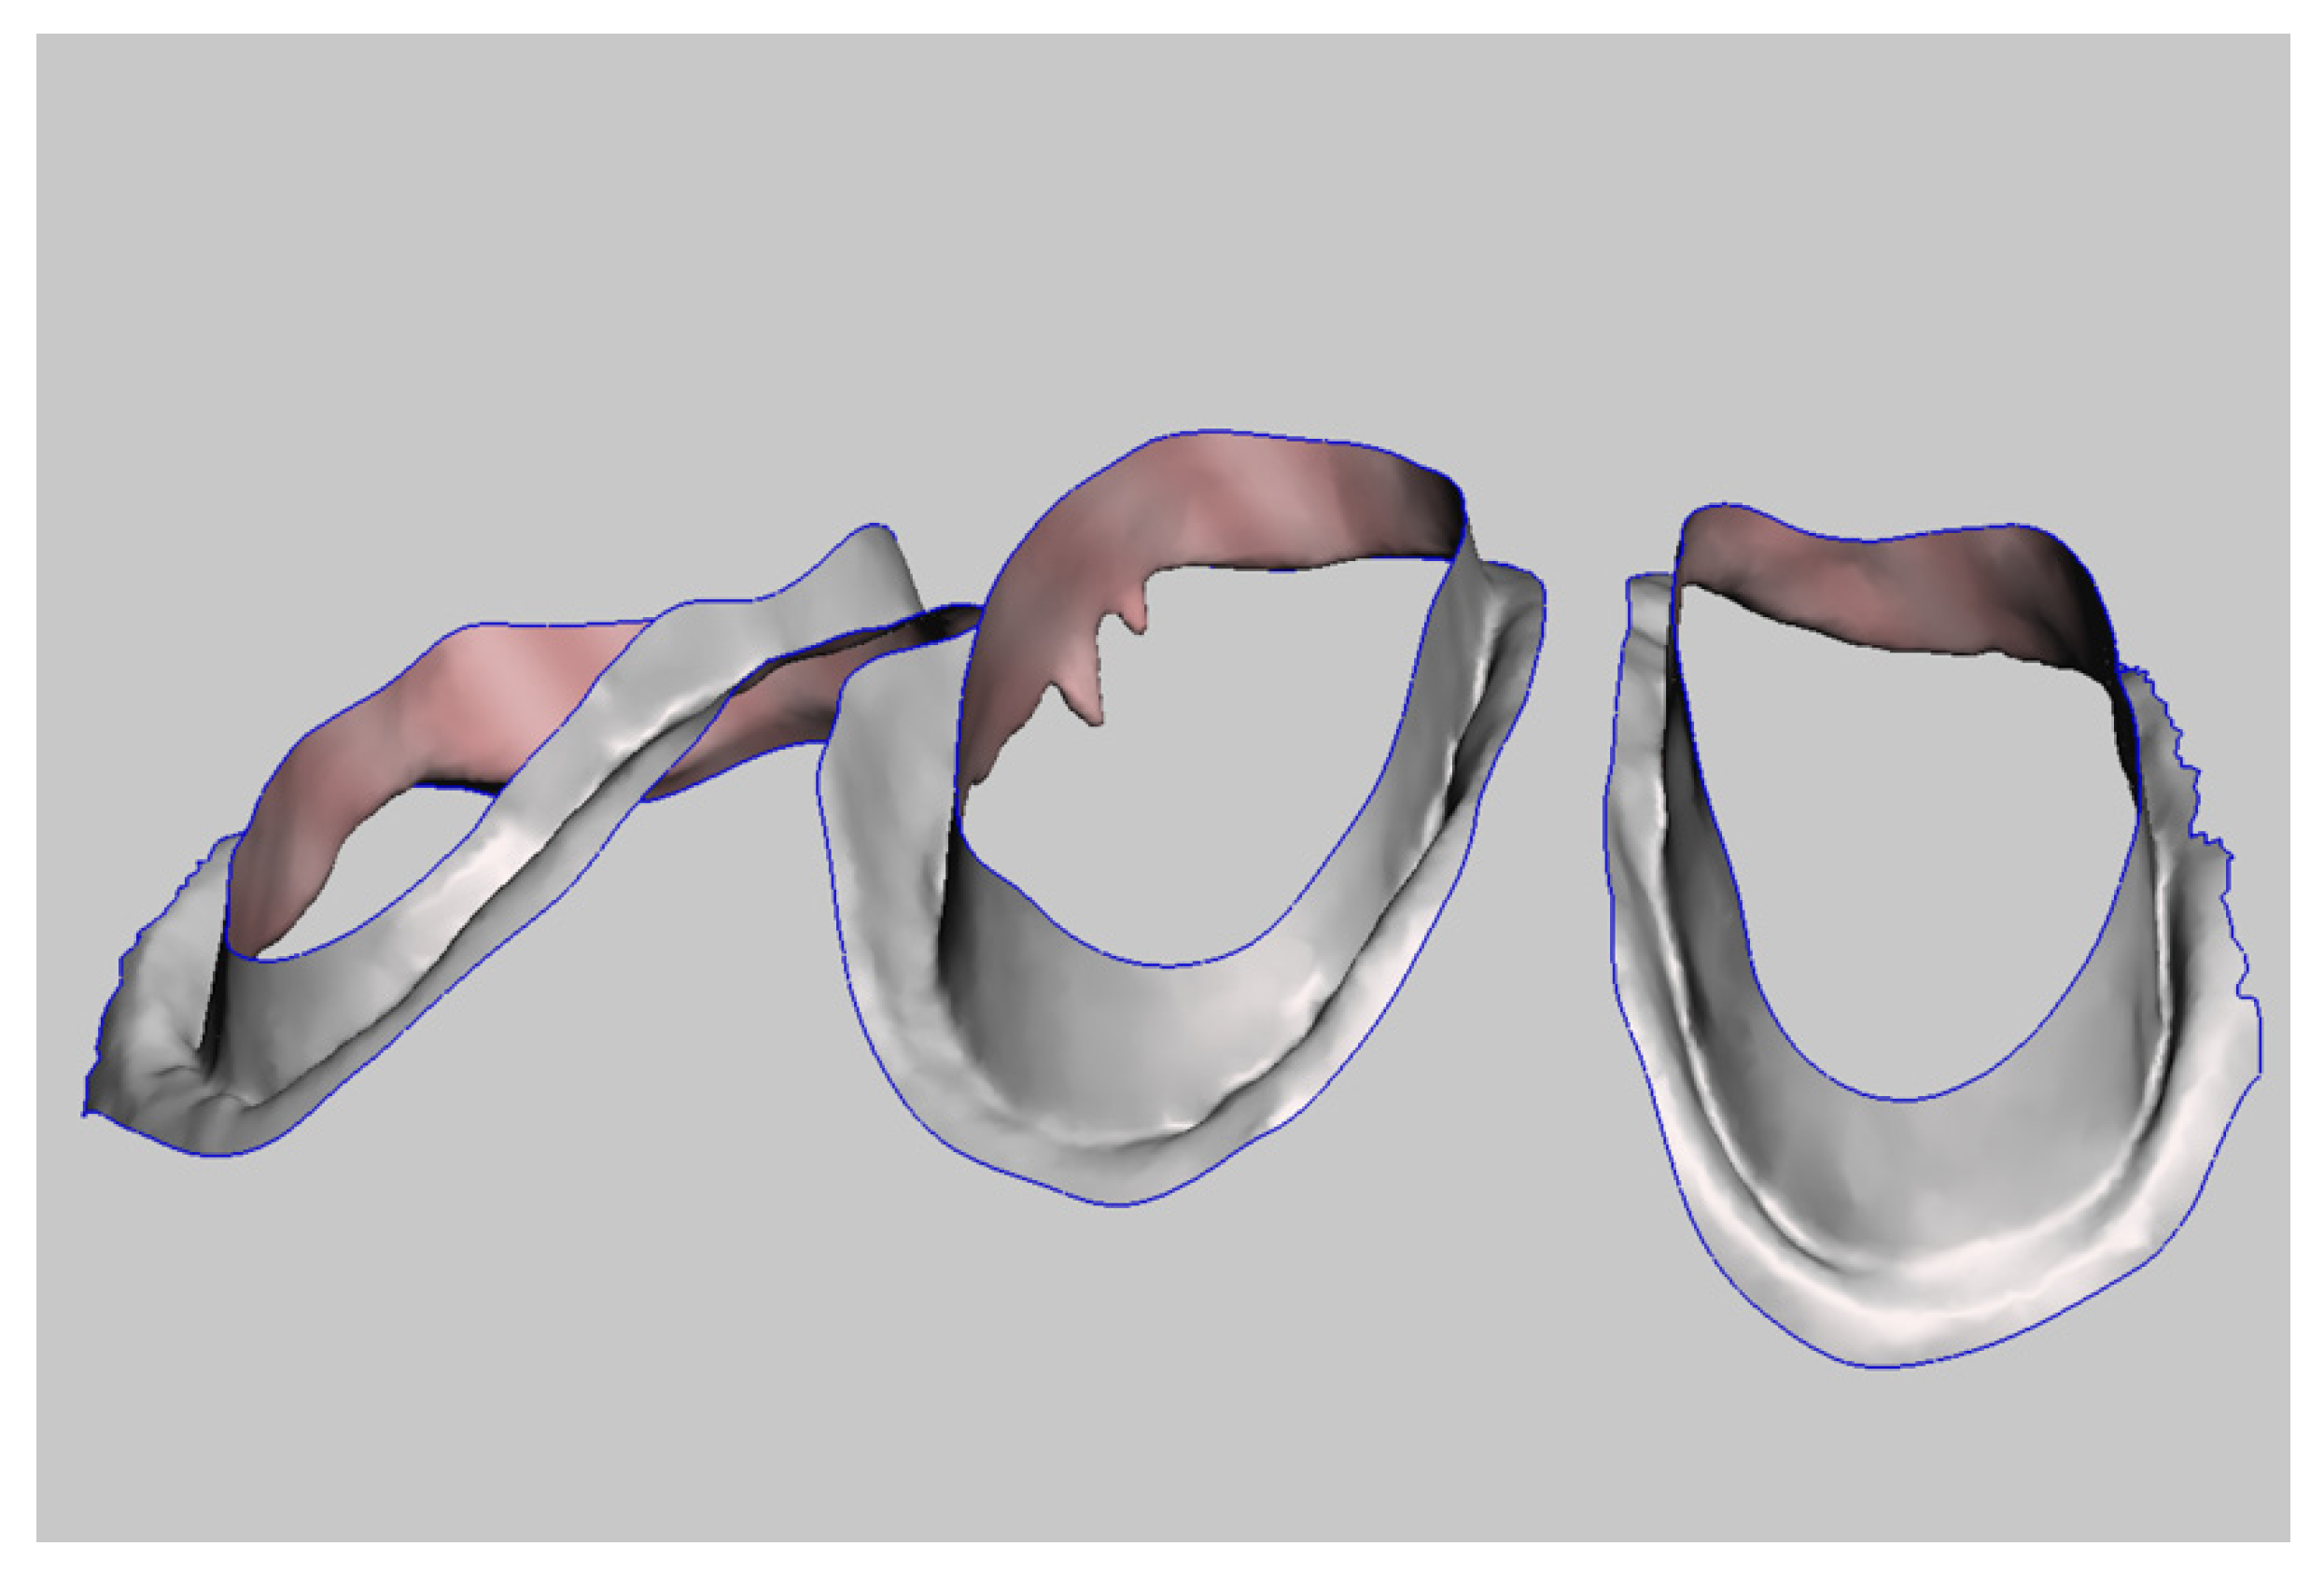

- Step C: Creation of the Master Model

Using MeshMixer, it is possible to detect and delete superimposed areas not intended to be part of the master model (Figure 11). From the abutment scan, we retain the coronal and medial third of the prepared teeth, whereas from the scan of the provisional restoration, we use the sulcus and finish line data (Figure 12 and Figure 13). Using the MeshMixer “Join” tool, we fuse the data in the two original STL files into a single, merged file (Figure 14), representing the subgingival zone. The final step is to match this file to the direct scan of the abutment. Then we import the file into Exocad and substitute the abutments of the original scan with the new ones that include more precise information on the subgingival zone. This last step is performed using the “Multi-die” tool (Figure 15). This method generates a master model in Exocad (Figure 16). When modelling the definitive restoration, the dental technician should consider that the master scan of the abutments, derived from the provisional restoration, does not provide information on the luting agent’s thickness. The operator should add this space using CAD software.

Figure 11.

Selection of the zones in the intraoral digital impression that are important to maintain.

Figure 12.

Coronal and median thirds derived from the intraoral digital impression.

Figure 13.

Subgingival zone derived from the scan of the provisional restoration.

Figure 14.

Deriving a unified file from two separate parts.